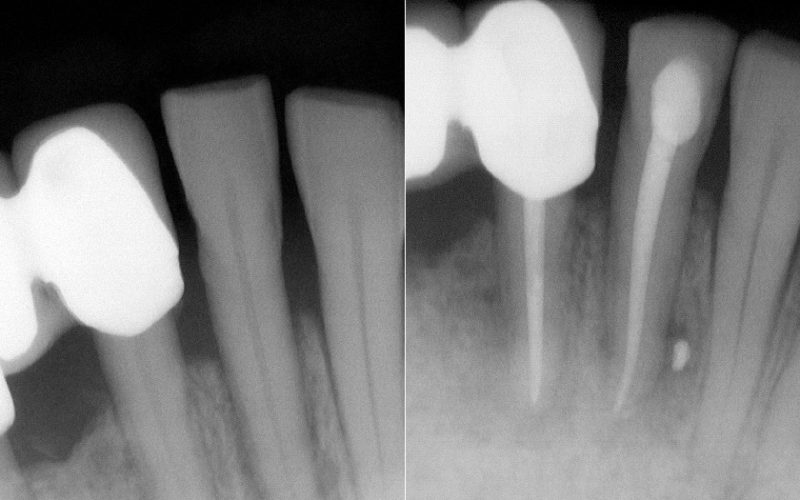

El primer paso y más importante es elaborar un buen diagnóstico: te haremos exploración, pruebas de vitalidad pulpar en clínica y utilizaremos las últimas herramientas digitales, como el escáner 3D y radiología digital, que nos dará la máxima información con la mínima radiación.